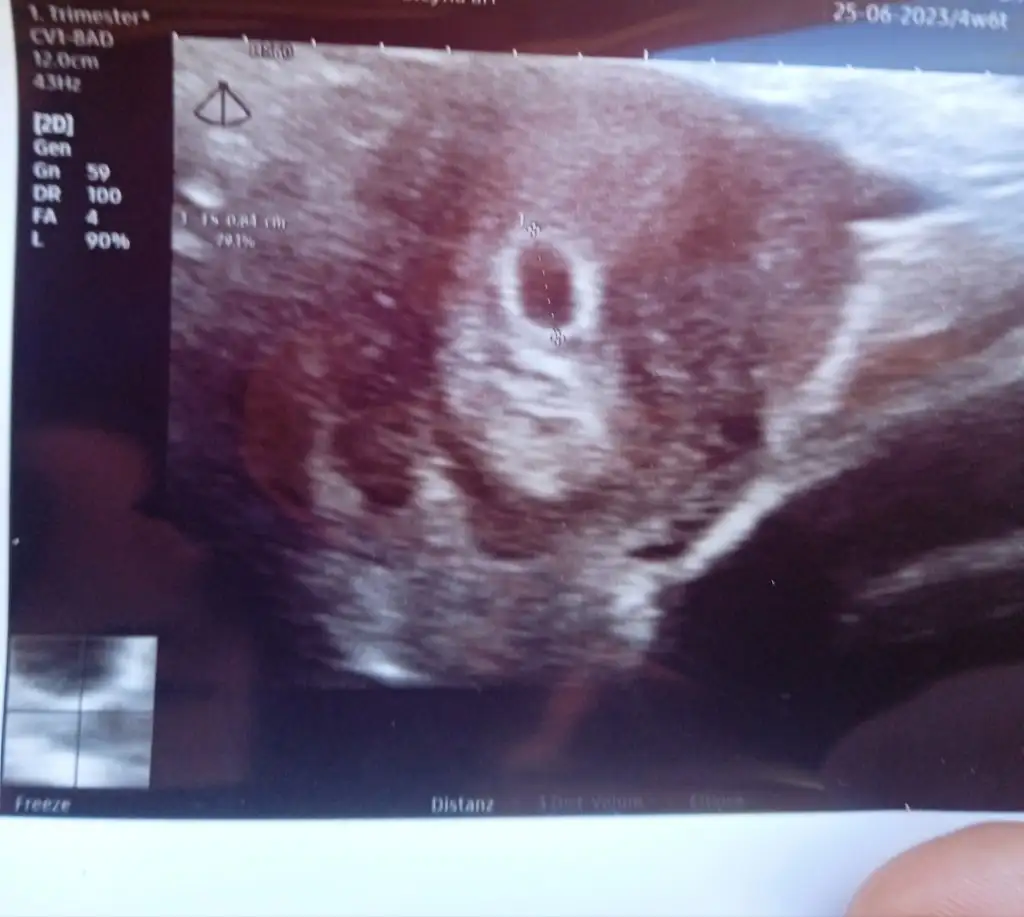

Çok şükür 6. Hafta da duydum canım lekelenmem gelmişti o gün doktorum çağırdı kontrol için kan sulandırıcı kesecekti baktı o an duymuştumÇok yakınız hafta olarak birbirimizekalp atışını duyabildin mi canım

Benim de 5+5 lekelenmem olunca gece nöbetçi doktor bulup ona gittik ama o duyamadi kalp atışını daha küçük dedi ilcedeyim eşimde çalışıyor haftaya Çarşamba izinli inşaallah o gün duyarım diyorum çok heyecanlıyımÇok şükür 6. Hafta da duydum canım lekelenmem gelmişti o gün doktorum çağırdı kontrol için kan sulandırıcı kesecekti baktı o an duymuştumsen duydun mu ya da ne zaman kontrol günün

Benim 6. Hafta oldu bugün, evet bugün ilk kez kontrole gittim doktorum izinliydi ben de çok erken dönemde gitmek istemedim bebişleri gördük çok şaşkınım haftaya da kalp atışını dinlemek için gidicezKaçıncı hafta sizin acaba bebekleri ilk kez mi gormustnz acaba

5+0'da gittik yolk görünmedi, 5+4'te yolk gördük, yarın 6+4 bebek ve kalp atışı duyacağız inşallahBebeği ne zaman gordun canım

İnşallah canım bu doktor ultrasonda kesemi de görememisti benim ertesi gün koşa koşa özele gittim kese gözüküyordu insan stres yapıyor ister istemez. Sanki fotoğrafta sol alt kısımda yuvarlak bir kısım görüyorum sen de bakarmisin5+0'da gittik yolk görünmedi, 5+4'te yolk gördük, yarın 6+4 bebek ve kalp atışı duyacağız inşallah![]()

Evet canım bence de var bi sonraki gidişinde iyice belirginleşirİnşallah canım bu doktor ultrasonda kesemi de görememisti benim ertesi gün koşa koşa özele gittim kese gözüküyordu insan stres yapıyor ister istemez. Sanki fotoğrafta sol alt kısımda yuvarlak bir kısım görüyorum sen de bakarmisin